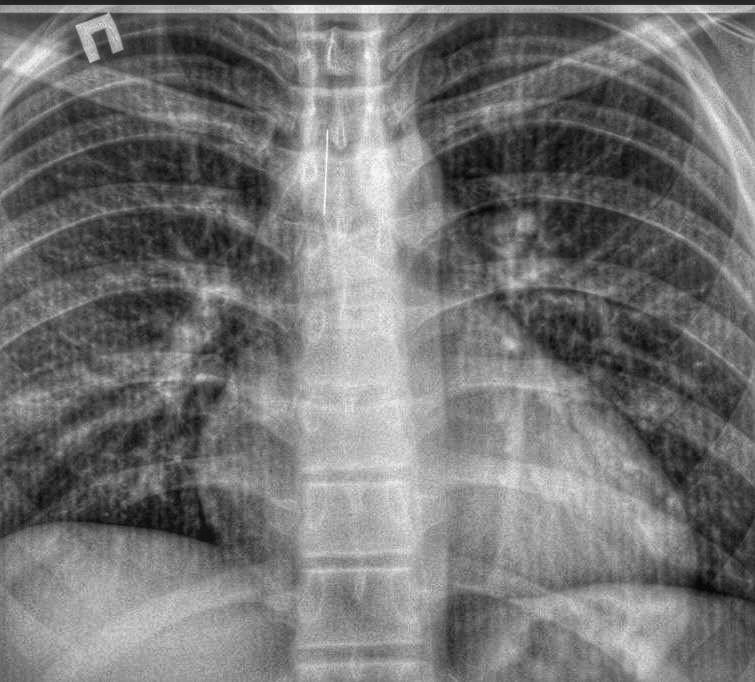

Клинический случай произошел 2 февраля. Подросток был доставлен в приемное отделение городской больницы из одного из поселков района с посторонним телом в трахеи.

Благодаря высокой квалификации дежурного хирурга и анестезиологической бригады, эндоскопическим методом было удалено инородное тело - игла длиной 4 см.

Подростку под наркозом провели бронхоскопию и достали шпильку, которая острым концом вонзилась в слизистую и никуда не двигалась.

Острый предмет мог вызвать перфорацию - пробить легкие или через стенку бронха попасть и в сердце. Последствия могли оказаться трагическими.